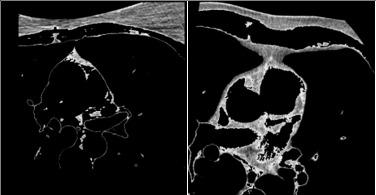

The term ‘Epicardial fat (ECF)’ is defined as the fat deposits on the heart muscles and their surroundings by a thin pericardium membrane [1]. It is essential to differentiate ECF from paracardial fat that is positioned outside the pericardium. This fat is often connected with other fat deposits in the area of the mediastinum [2], as shown in Figure 1. The ECF is known to release pro-inflammatory substances and contribute to atherosclerosis growth in the coronary arteries. The ECF volume holds clinical significance because of its association with major adverse cardiovascular events. Thus, an accurate ECF volume evaluation plays a major role in diagnosing cardiac conditions.

Figure 1. Heart fat CT images